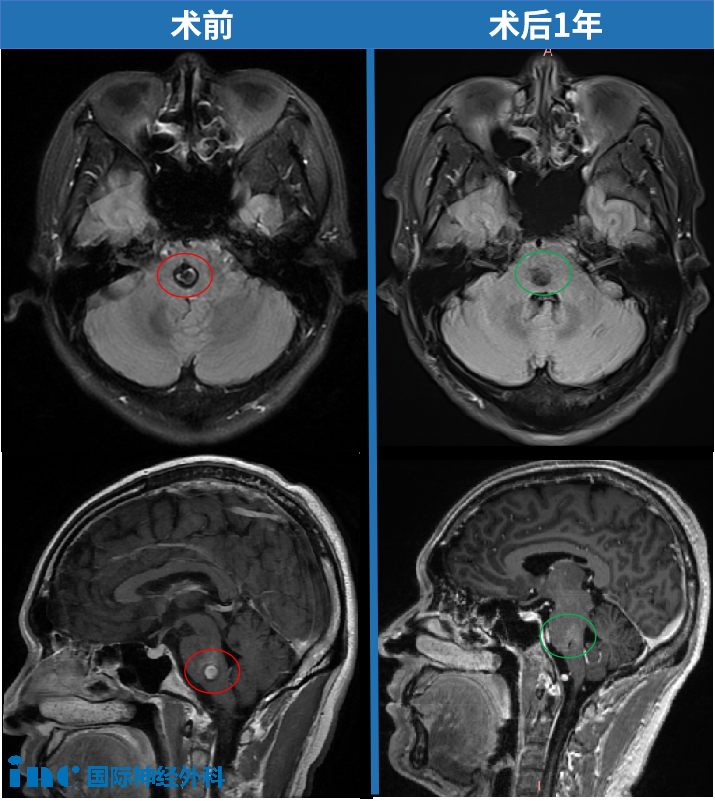

影像学检查显示:桥脑、延髓右侧部及右侧桥臂可见团片状T1WI低信号、T2WI高信号病灶,信号均匀,FLAIR序列呈高信号,边界清晰,尺寸约27 * 23 * 21mm,增强扫描未见明显强化,局部脑组织肿胀表现。

2023年12月,患者因轻微手指麻木就诊,初步检查发现脑干桥海区域存在0.8cm血管瘤伴出血征象。随诊一个月内,症状进行性加重,麻木范围扩展至手掌、手臂及下肢,复查显示病灶增大至1.5x1.2cm。

术后一年随访显示,患者运动功能完全恢复,行走、骑行等日常活动与常人无异。